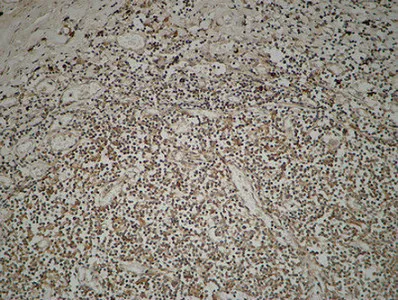

MPO Rabbit Polyclonal Antibody

Cat: APRab14056

Size1:50μl Price1:$118

Size2:100μl Price2:$220

Size3:500μl Price3:$980